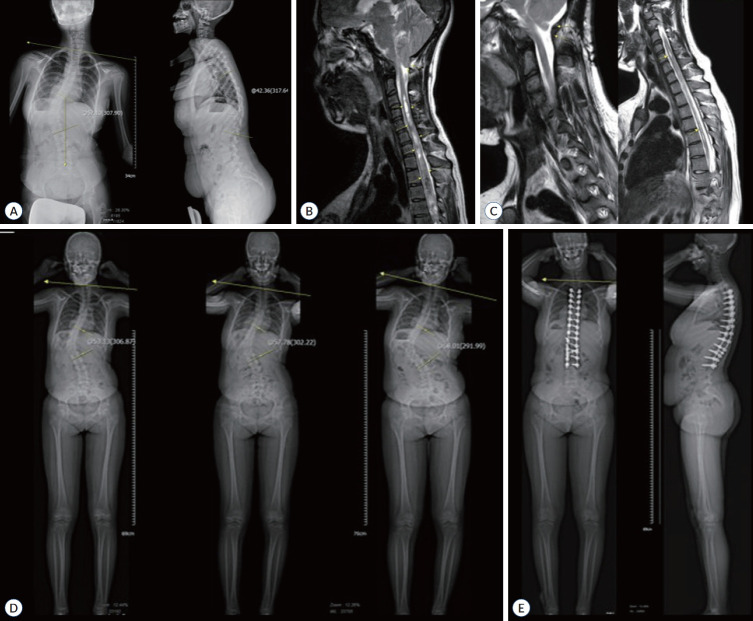

目的:本研究旨在评价由单一神经外科医生手术的青少年特发性脊柱侧凸(AIS)患者的临床和影像学结果。方法:在2011年1月至2024年1月期间,共调查了139例连续接受单一神经外科医生矫正手术的AIS患者。椎弓根螺钉节段内固定用于畸形矫正。评估人口统计学信息、采用Lenke分类的曲线结构类型、矫正程度、融合水平总数、并发症和临床/影像学结果。结果:大多数患者为青春期女孩(105 vs 34),平均年龄分别为15.9 vs 16.0。平均随访时间为4.5年(0.1 ~ 13.0年)。9例(6.6%)为左旋侧凸,其余130例为右旋侧凸。4例(2.8%)患者偶然诊断为伴脊髓空洞的Chiari畸形。在有Chiari畸形的患者中,2例(50%)有左旋侧凸。平均融合节数为11.2个。Cobb角在主结构曲率处的平均值为63.4°(43°-125°)。主要结构曲线的平均修正百分比为78.8%。术后最终SRS-22平均评分为4.3±0.4分,明显高于术前的3.8±0.5分(P < 0.001)。手术后,没有观察到神经功能缺损或需要重新定位螺钉的病例。一例患者接受翻修融合伸展手术治疗术后肩部不平衡。结论:经神经外科医生治疗的AIS患者具有可接受的临床和影像学结果。然而,AIS手术需要对小儿脊柱畸形有一个基本的了解,这是至关重要的。此外,脊柱外科医生在治疗左侧凸患者时应谨慎。

Results: Most patients were adolescent girls (105 vs. 34) with an average age of 15.9 vs. 16.0, respectively. The average duration of follow-up was 4.5 years (0.1-13.0). Nine patients (6.6%) had levoscoliosis, and the remaining 130 had dextroscoliosis. Chiari malformation with syringomyelia was incidentally diagnosed in four patients (2.8%). Of the patients having Chiari malformation, two (50%) had levoscoliosis. The mean number of fused levels was 11.2. The mean value of the Cobb angle of the major structural curvature was 63.4° (43°-125°). The major structural curve's average percentage of correction was 78.8%. The final postoperative SRS-22 average score significantly improved to 4.3±0.4 compared with the preoperative score of 3.8±0.5 (p<0.001). After the surgery, there were no observed cases of neurological deficits or need for screw repositioning. Revision fusion extension surgery was performed on one patient to treat postoperative shoulder imbalance.